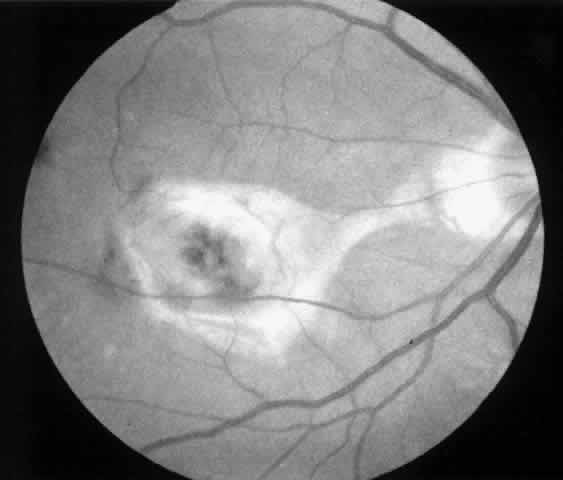

2. A 35-year-old patient developed an idiopathic subfoveal choroidal neovascular membrane with decrease in vision to 20/200 (6/60) (Fig. 9). He underwent surgical excision of the membrane. Laser was applied to the retinotomy at the conclusion of the case. One year after surgery, his visual acuity remained stable at 20/20 (6/6) (Fig. 10).

Fig. 9. Preoperative fundus photograph of a 35-year-old patient with idiopathic subfoveal neovascularization (case 2). Visual acuity is 20/200 (6/60).